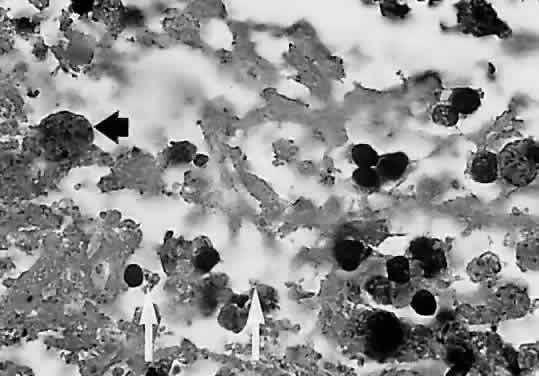

Researchers have had the opportunity to study the histopathologic characteristics of ocular toxoplasmosis in patients with AIDS and other immunosuppressant conditions at autopsy because disseminated toxoplasmosis is often a fatal disease (Fig. 5).61,77,106 Unlike disease in immunocompetent patients, parasites can occasionally be seen in the uveal tissue and there is scant cellular infiltration within retinal tissue. As with immunocompetent patients, however, the predominant site of infection appears to be the inner retina. The density of parasites is frequently greatest near blood vessels, suggesting newly disseminated disease rather than recurrence from tissue cysts within the retina.

Fig. 5. Light micrograph of a necrotic retinal lesion examined at the autopsy of a patient with AIDS and ocular toxoplasmosis. Tissue cysts (black arrow) and trophozoites (white arrows) are seen. There is little inflammatory material (hematoxylin and eosin). (Holland GN, Engstrom RE, Glasgow BJ et al: Ocular toxoplasmosis in patients with acquired immunodeficiency syndrome. Am J Ophthalmol 106:653, 1988. Copyright The Ophthalmic Publishing Company.)